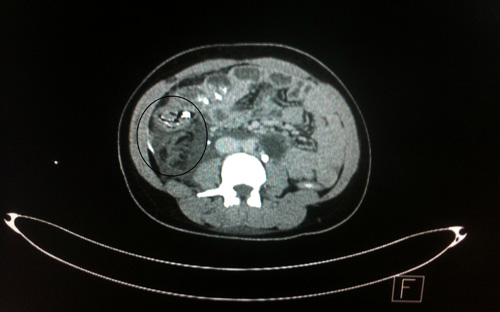

تدخّل جراحي ينقذ مصابة بطلق ناري  بجازان

جازان - عبده سيد:

نجح فريق طبي مكوّن من استشاريين من منسوبي مستشفى الملك فهد المركزي بجازان، في إنقاذ حياة مصابة سعودية 24 عاماً ، تعرّضت لطلق ناري عن طريق الخطأ من قِبل أحد أقاربها، أصابت منطقة الظهر من الأسفل وقد تجاوزت منطقة البطن. وقد أوضح الدكتور غازي النابلسي ، بأنّ المصابة تم استقبالها بقسم الطوارئ وجرى إسعافها بتقديم وحدات دم ومجموعة من السوائل، وقد أدخلت على الفور لغرفة العمليات لإجراء عملية سريعة لها ، حيث تسبب الطلق الناري في تهتك في الكلية اليمنى وثقب في القولون الصاعد وإصابة الوريد الكلوي الأيمن عند اتصاله بالأجوف السفلي وإصابة في الأوردة القطنية .. مؤكداً على توفيق الله عز وجل في إنقاذ حياة المصابة بعد إجراء الجراحة اللازمة لها.